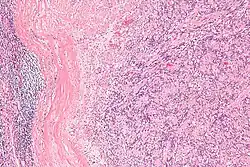

| Micrograph of an intranodal palisaded myofibroblastoma. H&E stain. | |

IPMs are diagnosed by examination of the tissue by a pathologist. They have a rim of peripheral lymphoid tissue (remnant of a lymph node) and consist of spindle cells with nuclear palisading. Red blood cell extravasation is common and blood vessels surrounded by collagen with (fine) peripheral spokes (amianthoid fibers) are usually seen.[2]

Immunostains for smooth muscle actin and cyclin D1 are characteristically positive. The main histologic differential diagnosis is schwannoma.

High mag.